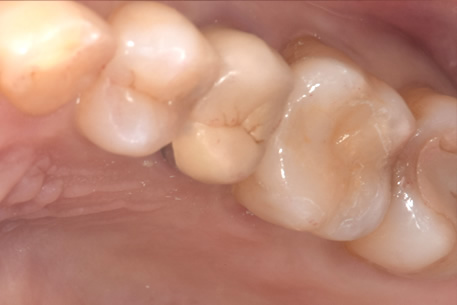

症例① セラミックインレー

治療前

治療後

年齢 60代女性

主訴 歯がしみる

治療方針 つめ物がすでに入っている歯です。そのため、見た目では虫歯があるかどうかわかりませんでしたので、レントゲンを撮影しました。すると、つめ物の中で虫歯になっていることがわかりました。虫歯は、とても大きくなっており神経に近い部分まで進行していました。

治療内容 神経が保存できるかどうか経過をみるために、覆罩といって、神経を守るための処置を行いました。2ヶ月ほど経過を見て、症状が出ないことを確認して、つめ物の型をとり、つめ物をいれていきました。

治療期間 3ヶ月

リスク・副作用 治療後に冷たいものがしみるなどの症状がでることがあります。つめ物を入れた後に痛みなどの症状が出てしまう場合は神経を取り除く治療が必要になります。

費用 ・セラミックインレー:55,000円(税込)

経過観察中に症状がでなかったため、セラミックのつめ物をいれていった。